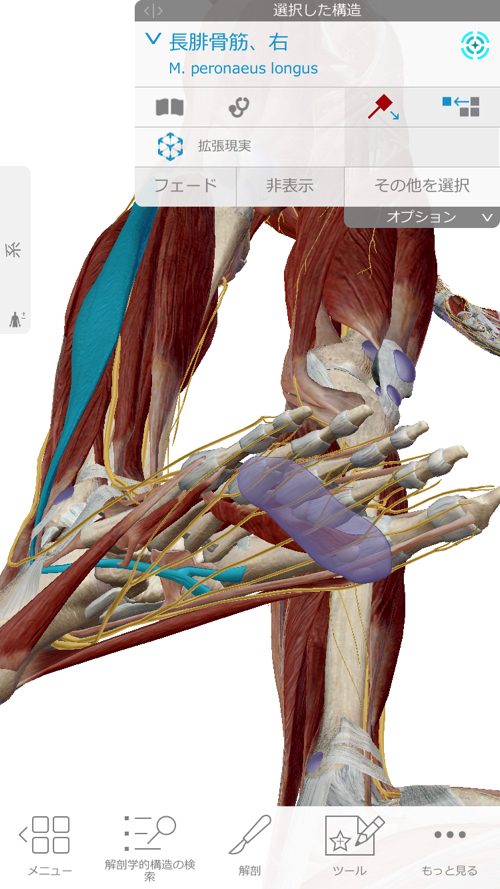

さらに膝に出来た余裕を利用してこの長腓骨筋を緩めて調整します。

今回、特にしっかりと調整したのはこの長腓骨筋です。

それは何故かというと・・

長腓骨筋は足裏からクルブシを通って膝の方へ繋がっていきます。

腓骨筋の先には親指を動かす短母趾屈筋

同じく趾に影響の大きい母趾内転筋にも連携しています。

長腓骨筋は膝・足首・足裏・足の指に全て影響するのがお分かり頂けたと思いますが

足だけ、膝だけ・腰だけと部分部分で切り取った見方では、脚全体の硬直や捩れ、微妙なズレなどは絶対に分からないし、レントゲンやMRIには、この長腓骨筋などの硬直やヨジレは写らないのです。